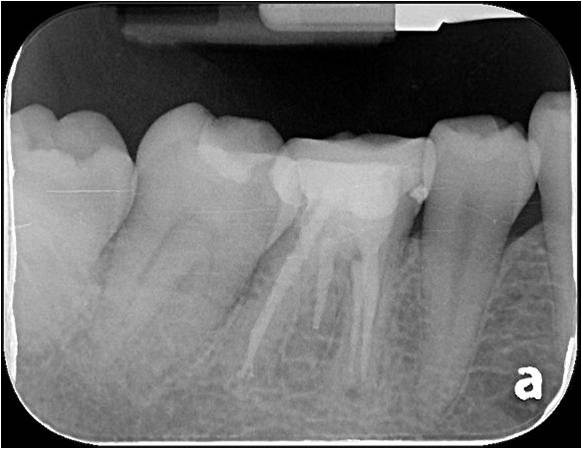

治療前,根管治療後組織良好